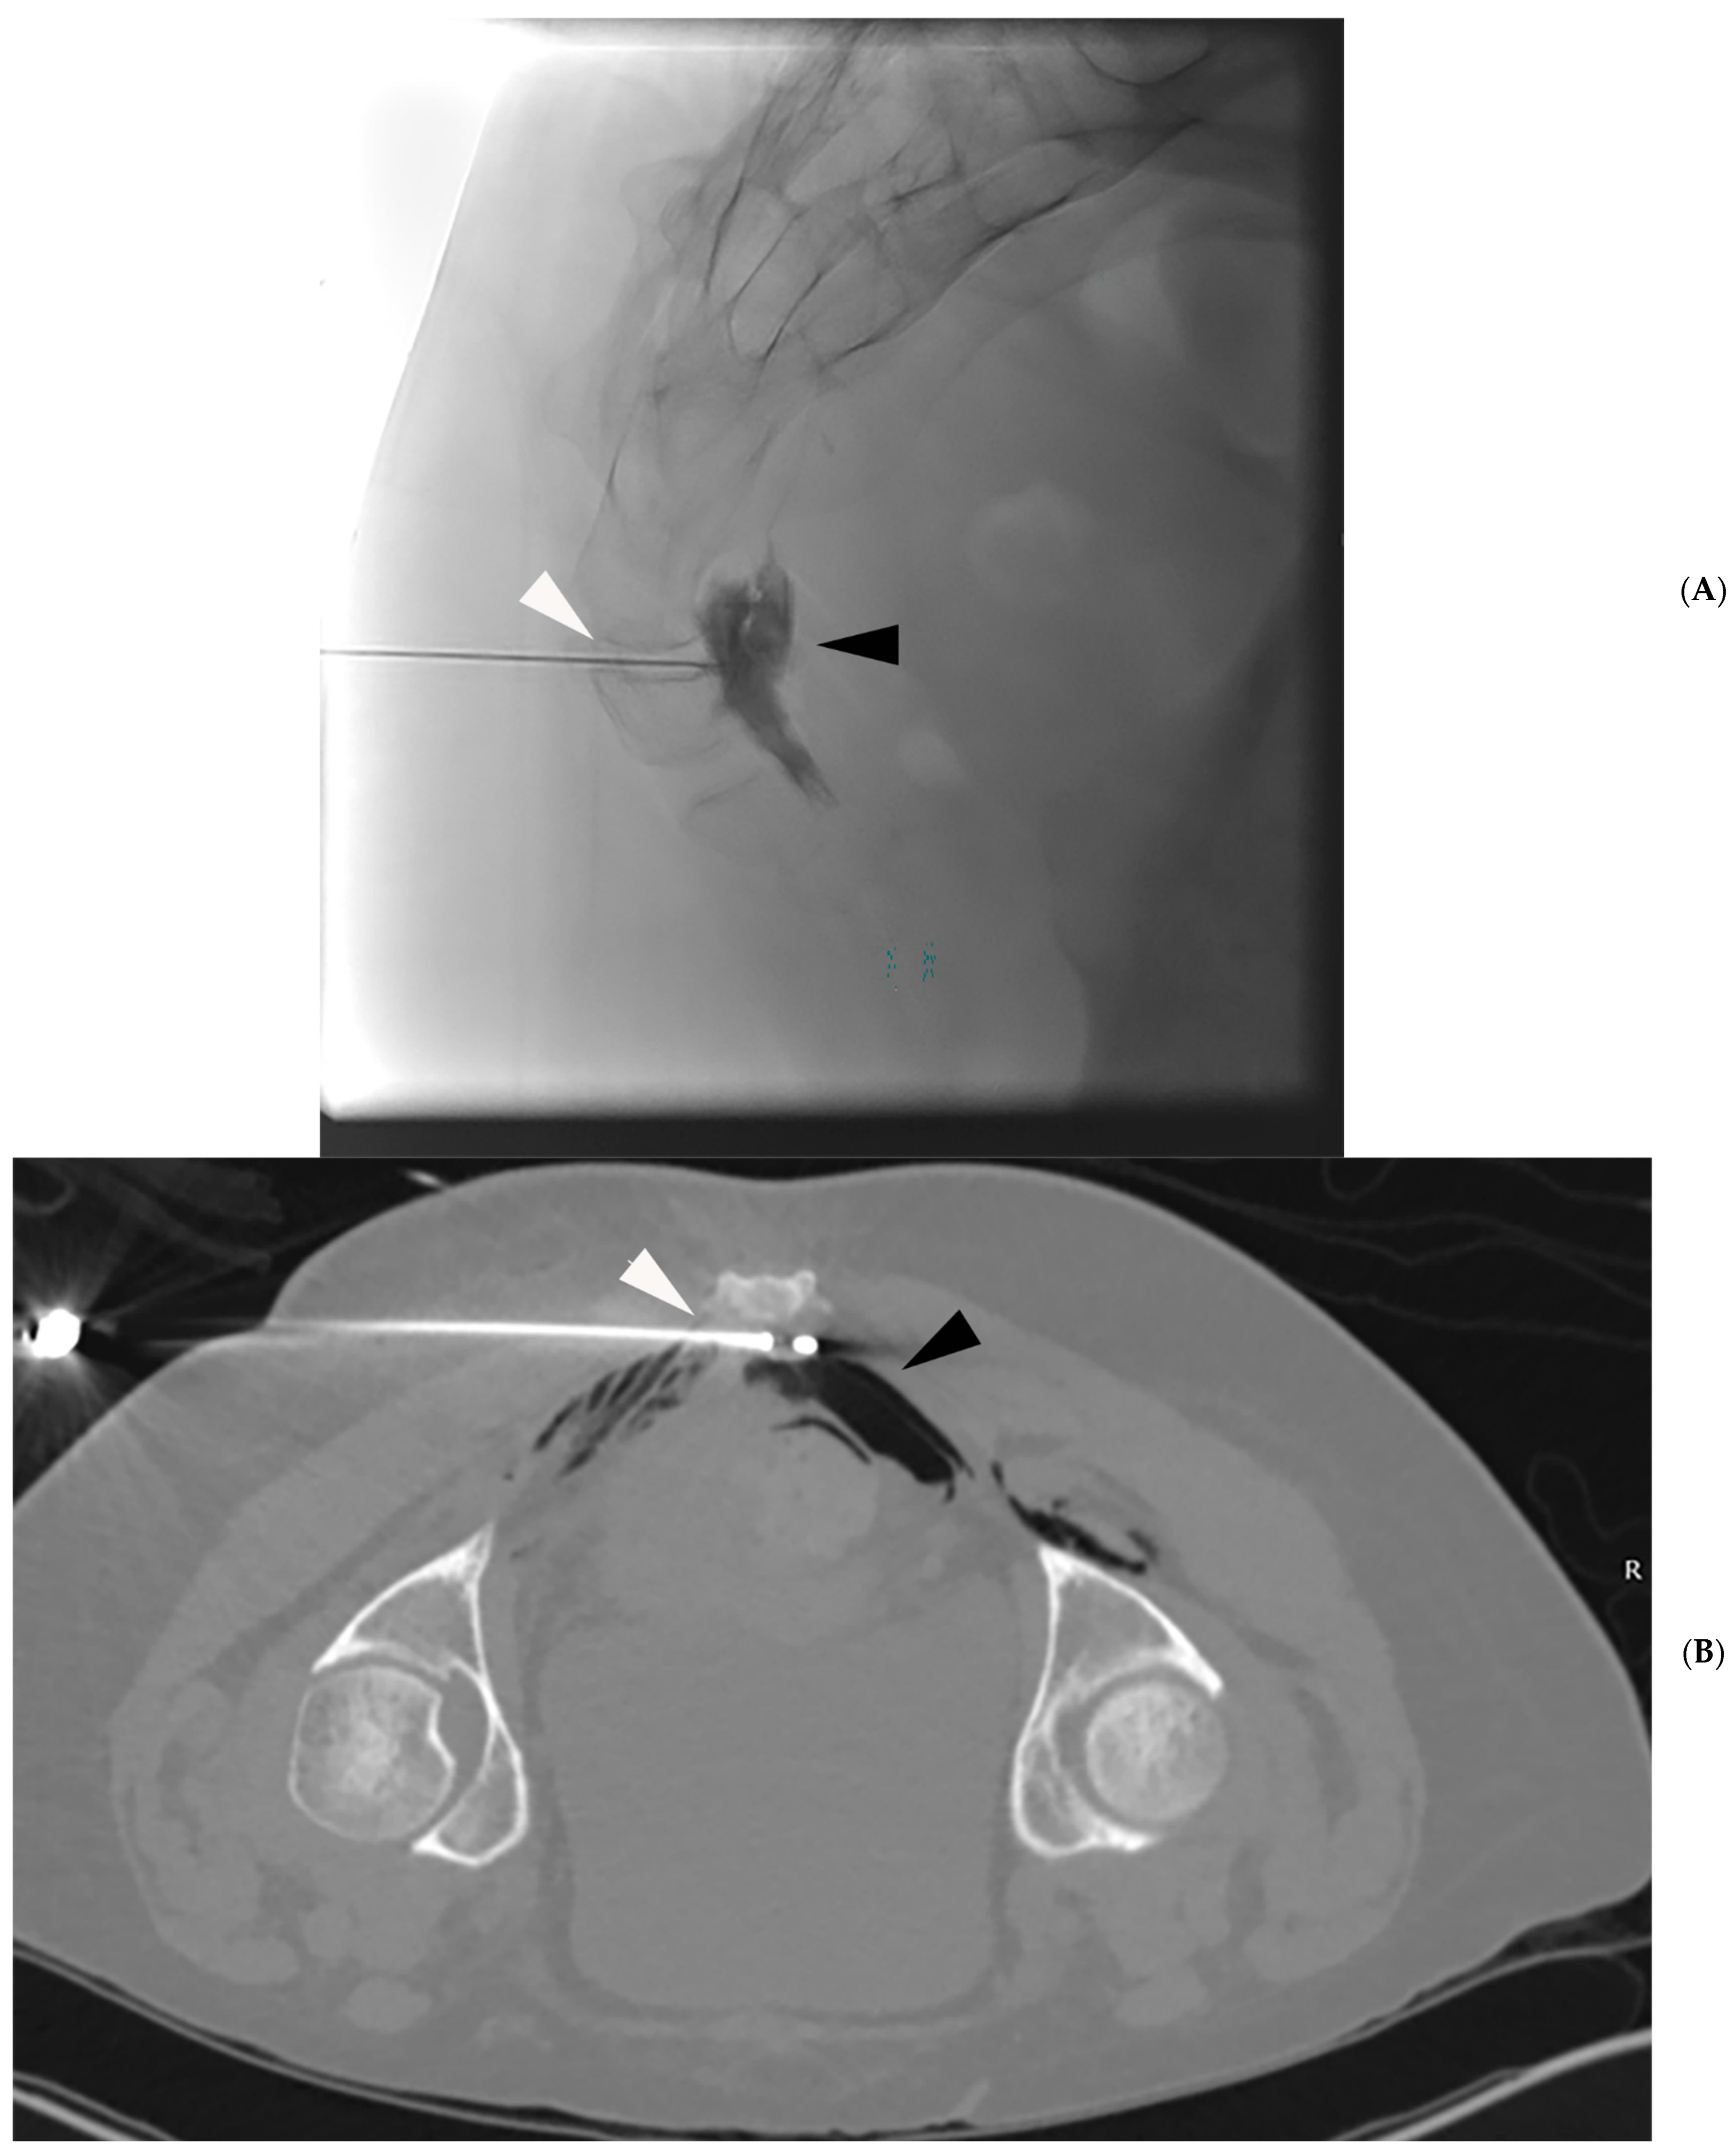

- Prologo, J.D.; Manyapu, S.; Bercu, Z.L.; Mittal, A.; Mitchell, J.W. Percutaneous CT-Guided Cryoablation of the Bilateral Pudendal Nerves for Palliation of Intractable Pain Related to Pelvic Neoplasms. Am. J. Hosp. Palliat. Care 2020, 37, 619–623. [Google Scholar] [CrossRef] [PubMed]

- Prologo, J.D.; Lin, R.C.; Williams, R.; Corn, D. Percutaneous CT-guided cryoablation for the treatment of refractory pudendal neuralgia. Skeletal Radiol. 2015, 44, 709–714. [Google Scholar] [CrossRef]